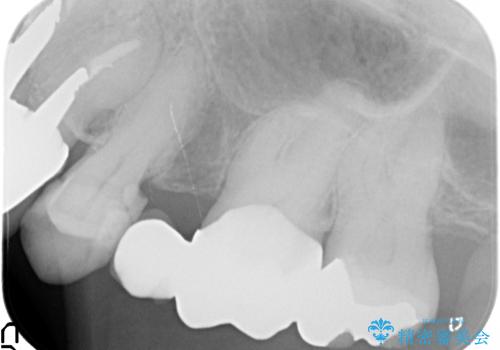

- 昔治療した左上56の延長ブリッジをきちんと治療しなおしたいといらっしゃった方の症例です。

古いブリッジを除去後、オールセラミッククラウンによる補綴を行いました。